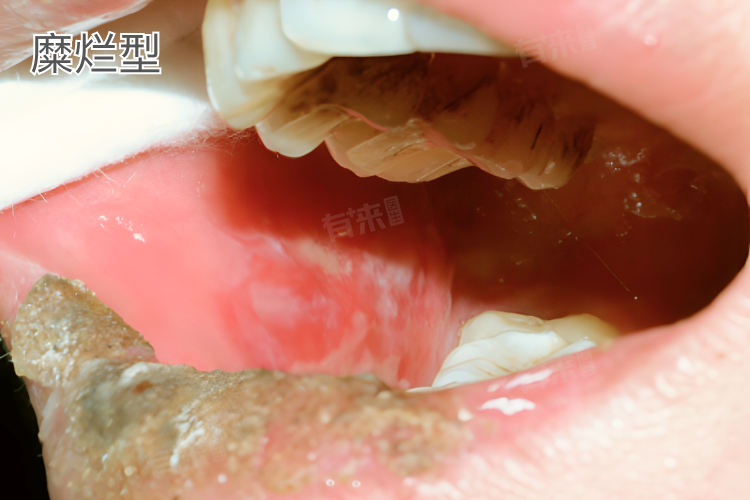

糜烂型

- 此型相对来说症状较为严重,口腔黏膜在疾病发展过程中出现破损、糜烂,糜烂面往往较小但数量可能不止一处,形状不规则,边界不清晰,表面有渗出物,呈现出淡黄色或灰白色,周围的黏膜组织会有红肿现象,看起来显得 “脏兮兮” 的。

- 患者会感觉到明显的疼痛,尤其是在进食刺激性食物、说话、吞咽时,疼痛会加剧,严重影响日常生活,而且糜烂面愈合相对较慢,容易反复出现。